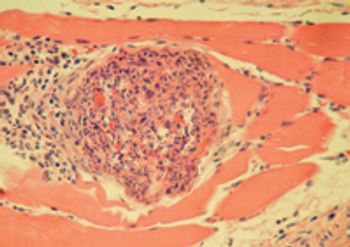

Gastrointestinal parasites are insidious causes of disease in cats. Protozoan parasitic infections in particular can be difficult to detect because there are often no signs of disease, or the signs, such as diarrhea, are nonspecific. But these infections must be uncovered and cured before they cause serious disease or spread to housemates or even owners.